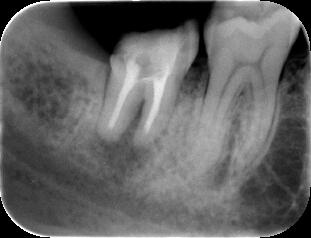

(1)不十分な根管(神経の通っていた管)治療が原因で右下の顎が腫れています。(↑病巣

当初は抜歯を考慮しました(上左図)が、根の治療を丁寧に行うことによって、半年後には

ほぼ問題の無い程度(上右図)にまで骨が修復され十分に機能が回復されました。